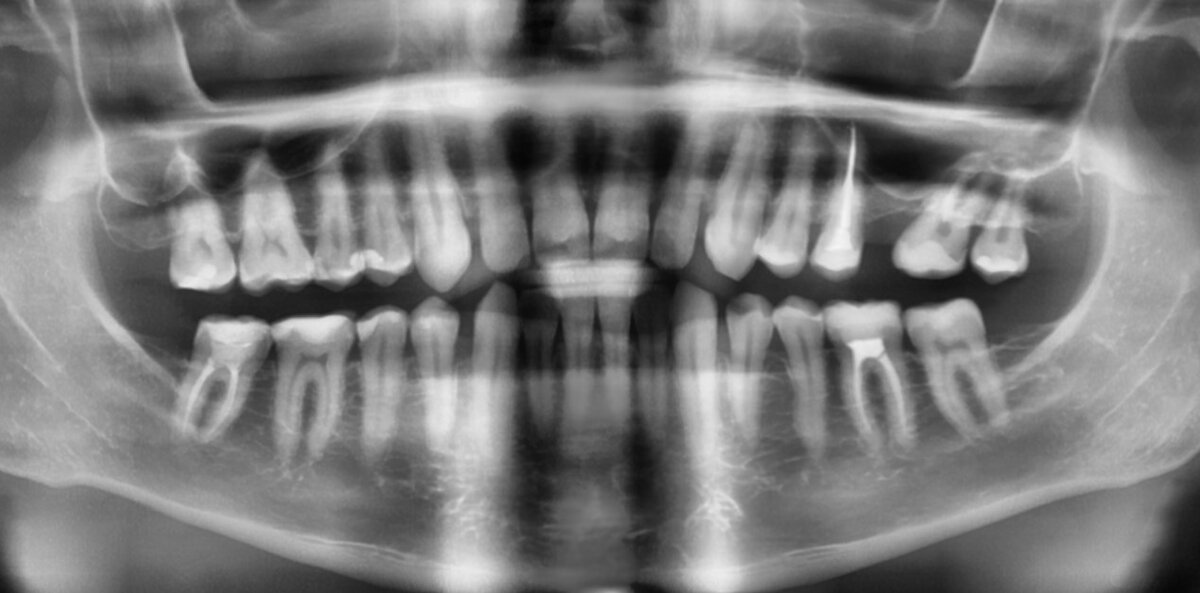

ортопантомограмма  от 5 декабря 2022 года

Выглядит вроде бы всё не так уж и плохо на первый взгляд. Видим что нет 1 зуба на верхней челюсти и костная ткань там убыла. Есть какие-то пломбочки, 3 зуба без нерва.

Итак, что на самом деле мы имеем? К 32 годам я уже бывалый стоматологический пациент.

У меня было 13 пломб (на всех жевательных и практически всех премолярах), затем я поменял 4 пломбы на 4 керамические вкладки на левой стороне. Есть 1 зуб мудрости слева сверху (остальных не было в зачатках). Да у меня только 1 зуб мудрости был и есть. И нет 1 зуба под номером 26 (его удалили около 13 лет назад).